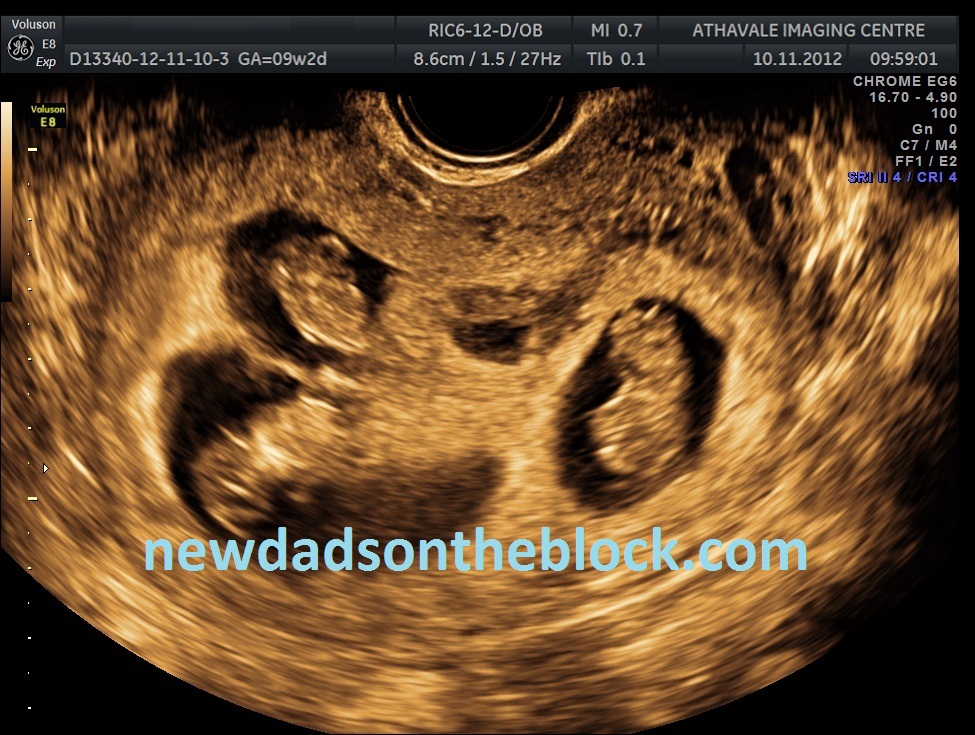

Good news: Matt and I are eleven weeks along with healthy twins! 🙂

Two healthy babies is wonderful news, of course. However, we were pregnant with triplets initially. Our medical team in India let us know their concerns about the health and well-being of the three babies, and our gestational carrier, due to the multiple pregnancy. Their concern was great enough that they let us know they felt it medically necessary to reduce the pregnancy from triplets to twins.